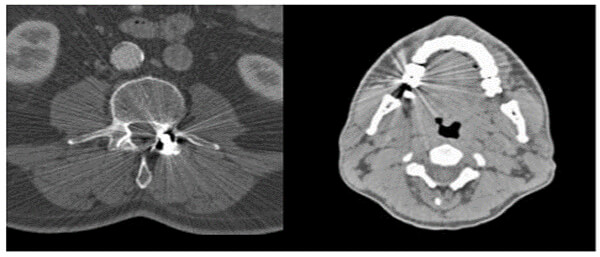

Metal implants such as shrapnel, surgical clips, pacers, joint prostheses, wires, pedicle screw placement, stenting, usually undergo follow-up CT imaging. These metallic implants lead to severe streak and shadow artifacts in CT images that superimpose the structures of interest and deteriorate image quality. This is because metallic objects are a high-density material, which is strongly scattered to the transmitted x-ray beam during CT examination.

Various metal artifact reduction techniques have been developed to reduce metal artifacts, and the most commonly used reconstruction algorithm for CT has filtered back projection (FBP), interpolation methods, and iterative reconstruction methods.

The formation of these artifacts is due to the impossibility of algorithms to take into consideration the very high-density values. This causes misinterpretation of images as the metals absorb more of the x-rays. This absorption creates shadows.

Compare the density of the prosthetic materials in these images all taken at 120 kV. As you can see, gold has the highest Hounsfield units.

As part of an operator’s role, patients should be asked to remove jewelry and dentures before starting the scans. This assists in avoiding some metallic related artifacts.

For non-removable items such as dental fillings and joint prosthesis, it is sometimes possible to use gantry angulation to exclude the metal inserts from scans of nearby anatomy.

It is also possible to adapt the kV values used based on the visualized structure or to use dual-energy protocols. Notice the difference in streaking in these three images.

Streaking caused by over ranging can be greatly reduced using special software corrections. Manufacturers use a variety of interpolation techniques designed to substitute the over ranged values in attenuations’ profile.

However, there is always a detail loss around the metal/tissue interface, which is often the area of interest in diagnosis.

This image shows the effectiveness of metal reduction artifact software. Notice how much better the resolution is in the image on the right.

Let’s look at the differences in these four images taken at different dual energy levels. Compare the streak artifacts with the 80kV, 140 kV, the mixed acquisition of 140kV and 80 kV and the last at 140 keV.